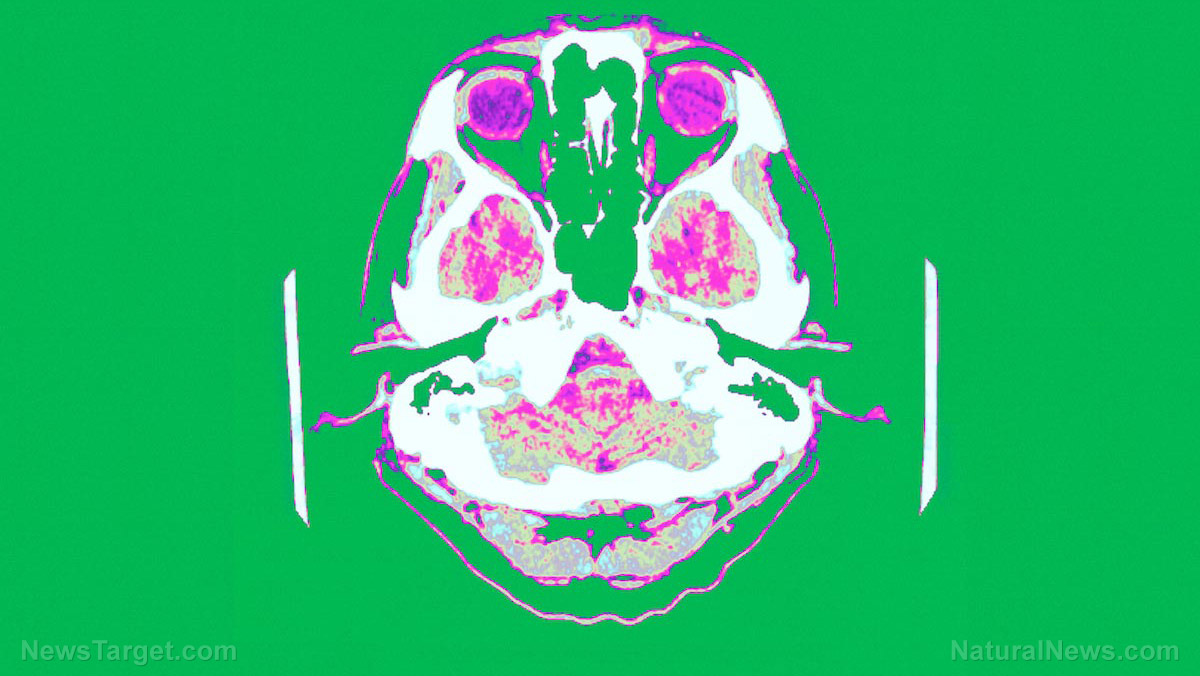

A Japanese study combined two different techniques in order to keep track of live changes inside the brain. This new real-time observation method enables a brand new field of research dubbed "real-time metabolomics," an article in Alpha Galileo states.

Their method combined probe electrospray ionization (PESI) and tandem mass spectrometry (MS/MS). The former technique sprayed ions from a sharp, solid needle while the latter provided very detailed images of the internal structure and properties of tiny substances such as the metabolites produced by a living organism. (Related: Take fish oil OR blueberry powder for better brain health.)

The Nagoya University research team combined a probe electrospray ionization unit with a tandem mass spectrometer instrument. The tip of the PESI unit's solid needle has a very thin diameter of 700 nanometers. It can draw samples and ionize targets with the least amount of disruption of sensitive processes in the brain.

An anesthetized mouse served as the initial test subject of the new PESI/MS/MS analyzer. The researchers reported identifying eight brain metabolites associated with central energy metabolism. The in vivo real-time monitoring process took all of 20 seconds.